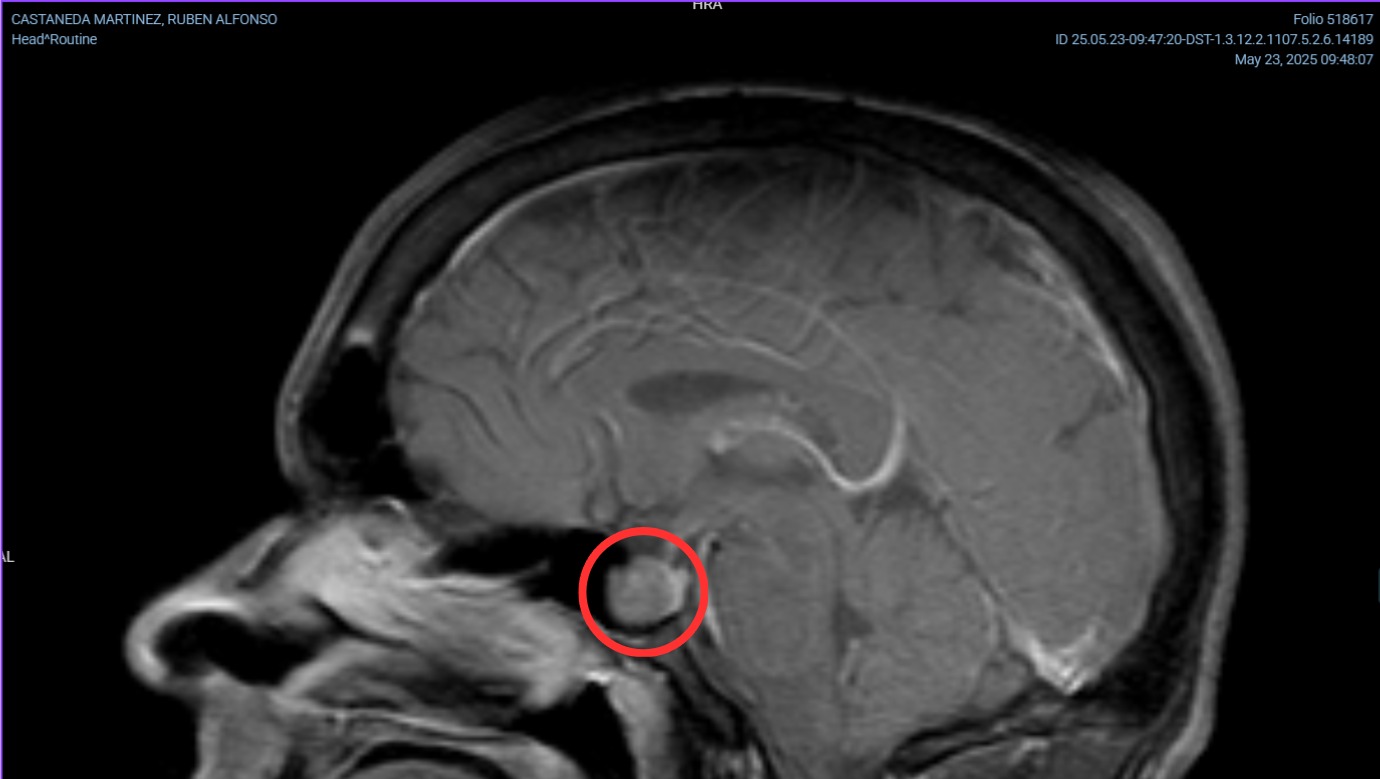

Una resonancia magnética de cráneo confirmó el diagnóstico: tengo un tumor en mi cerebro, en la glándula pituitaria (también conocida como hipófisis).

Después de varios estudios, se identificó que el tumor secreta hormona de crecimiento (GH) y hormona adrenocorticotrópica (ACTH), que estimulan la producción de IGF-1 y cortisol, respectivamente. Esta sobreproducción causa dos enfermedades simultáneas en mí: el exceso de GH provoca acromegalia, y el exceso de cortisol, enfermedad de Cushing.

Requiero de neurocirugía para extirpar el tumor, y después debo realizar un seguimiento hormonal con un endocrinólogo, además de resonancias magnéticas periódicas para ver si hay remisión.